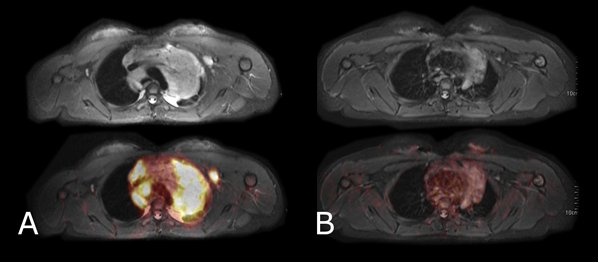

[18F]FDG-Glukosestoffwechsel-PET-MRT von Tumoren: Links: Kindliches Lymphom mit intensivem Zuckerstoffwechsel (A) vor Chemotherapie. Rechts: Nach Chemotherapie ist das Tumorgewebe in der MRT noch deutlich sichtbar, der Zuckerstoffwechsel ist nahezu vollständig normalisiert (B).